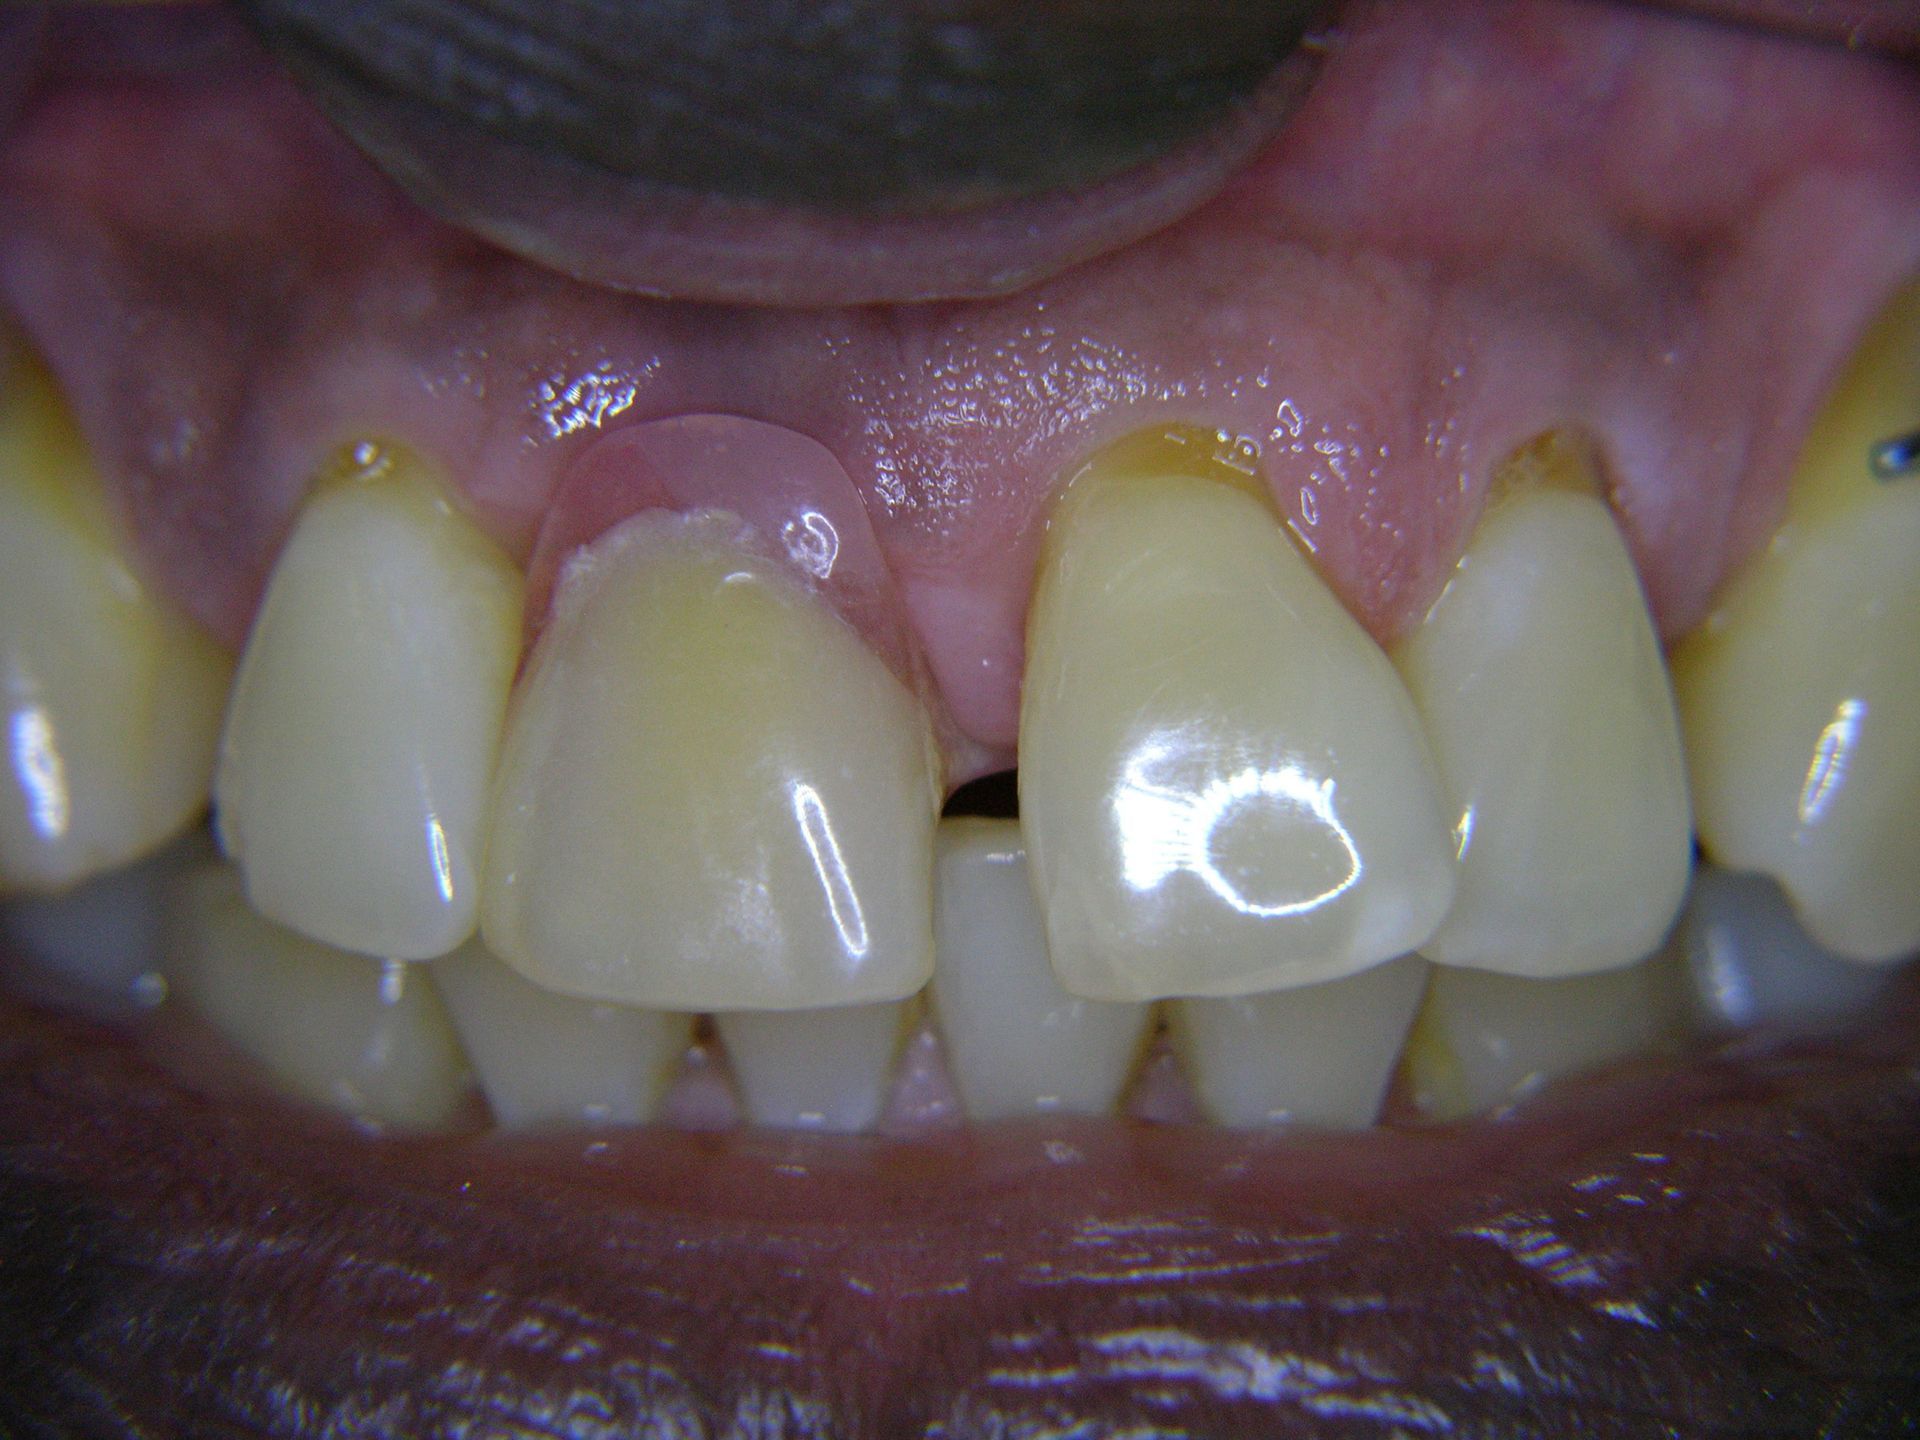

Beispiele von Versorgungen